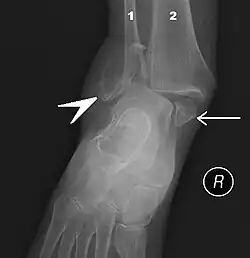

Fracture of both sides of the ankle with dislocation as seen on anteroposterior X-ray. (1) fibula, (2) tibia, (arrow) medial malleolus, (arrowhead) lateral malleolus

An ankle fracture is a break of one or more of the bones that make up the ankle joint.[21] Symptoms may include pain, swelling, bruising, and an inability to walk on the injured leg.[21] Complications may include an associated high ankle sprain, compartment syndrome, stiffness, malunion, and post-traumatic arthritis.[21][22]

Ankle fractures may result from excessive stress on the joint such as from rolling an ankle or from blunt trauma.[21][22] Types of ankle fractures include lateral malleolus, medial malleolus, posterior malleolus, bimalleolar, and trimalleolar fractures.[21] The Ottawa ankle rule can help determine the need for X-rays.[22] Special X-ray views called stress views help determine whether an ankle fracture is unstable.